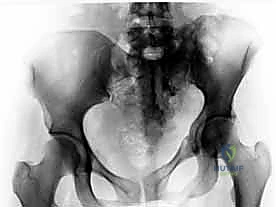

2. الأشعة السينية (X-rays): توفر نظرة أولية سريعة على كسور الحوض (AP, Inlet, and Outlet views).

3. التصوير المقطعي المحوسب (CT Scan): وهو المعيار الذهبي (Gold Standard) لتشخيص كسور الحوض والعجز. يقوم الدكتور هطيف باستخدام تقنية إعادة البناء ثلاثي الأبعاد (3D Reconstruction) لفهم هندسة الكسر بدقة متناهية قبل الدخول إلى غرفة العمليات.